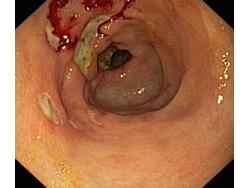

Wrzód trawienny